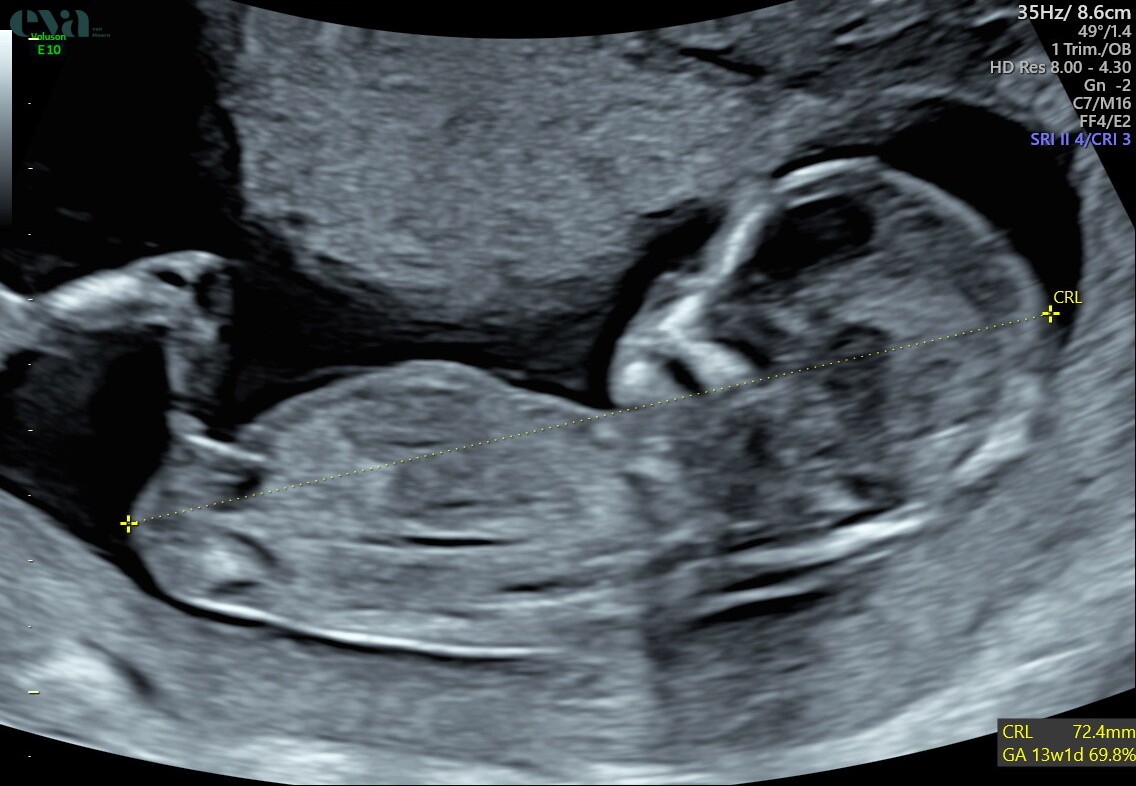

Hej jestem w 14 tyg ciąży jak dla mnie to dziewczynka , lekarz nie chcę powiedzieć . Może ktoś miał podobnie :) nie mogę się doczekać

• IMG_6315.jpeg

153,4 KB · Wyświetleń: 3 175

Kuleczka, więc jak dla mnie chłopak. Mówię to jako mama czterech chłopaków.

Ja tam kuleczki nie widzę gdzie jest 😀